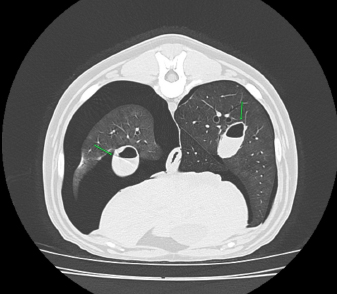

Case details for each of the five dogs included in the study are listed in Table 1. The etiology of the pneumothorax were congenital pulmonary bullae in two dogs, traumatic in one (road traffic accident), lungworm infection in one, and unknown in the remaining dog. Dog number 1 presented a large pulmonary bulla in the right cranial pulmonary lobe (Fig. 1). Dog number 2 presented four bullae: two in the medial aspect of the left cranial lung lobe (17 mm each), one in the caudal aspect of the left caudal lung lobe (26 mm), and another in the caudal border of the left caudal lung lobe (36 mm) (Fig. 2). Dog number 3 presented a large bulla measuring 33 mm in the medial aspect of the right middle lung lobe and around 10 blebs measuring from 3 to 6 mm in the ventral border of both right and left cranial lung lobes. Dog number 4 developed multiple small bullae and a larger one measuring over 10 cm, 24 hours after treatment of lungworm with spot on Imidacloprid and Moxidectin, which were responsible for a moderate unilateral pneumothorax (Fig. 3). Despite the severity of the pneumothorax, dog number 5 did not show any lesions on the computed tomography (CT) scan that could clearly explain its origin. Only one chest tube was placed in dogs 1, 2, 3, and 4. Two were placed in dog 5.

Fig. 2. CT transverse image of the thorax of the dog number 2 with pneumothorax secondary to multiple bullae after a road traffic accident. A bulla in the right hemithorax and another in the left are indicated in the image (arrows).